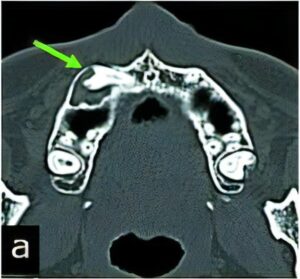

のう胞

のう胞は、何らかの理由で“水を含んだふくろ”ができてしまう病気です。特に顎骨は、のう胞ができやすいと言われています。

顎骨ののう胞では、虫歯から発生する「歯根嚢胞」が大半を占めていますが、くちびるにできる「粘液嚢胞(唾液が貯まった嚢胞)」や「含歯性嚢胞(埋伏歯にできる)」など様々な種類があります。

当科ではCT、MRI、病理組織診(良性悪性の確認検査)などの検査・診断、および治療(手術)を行っています。